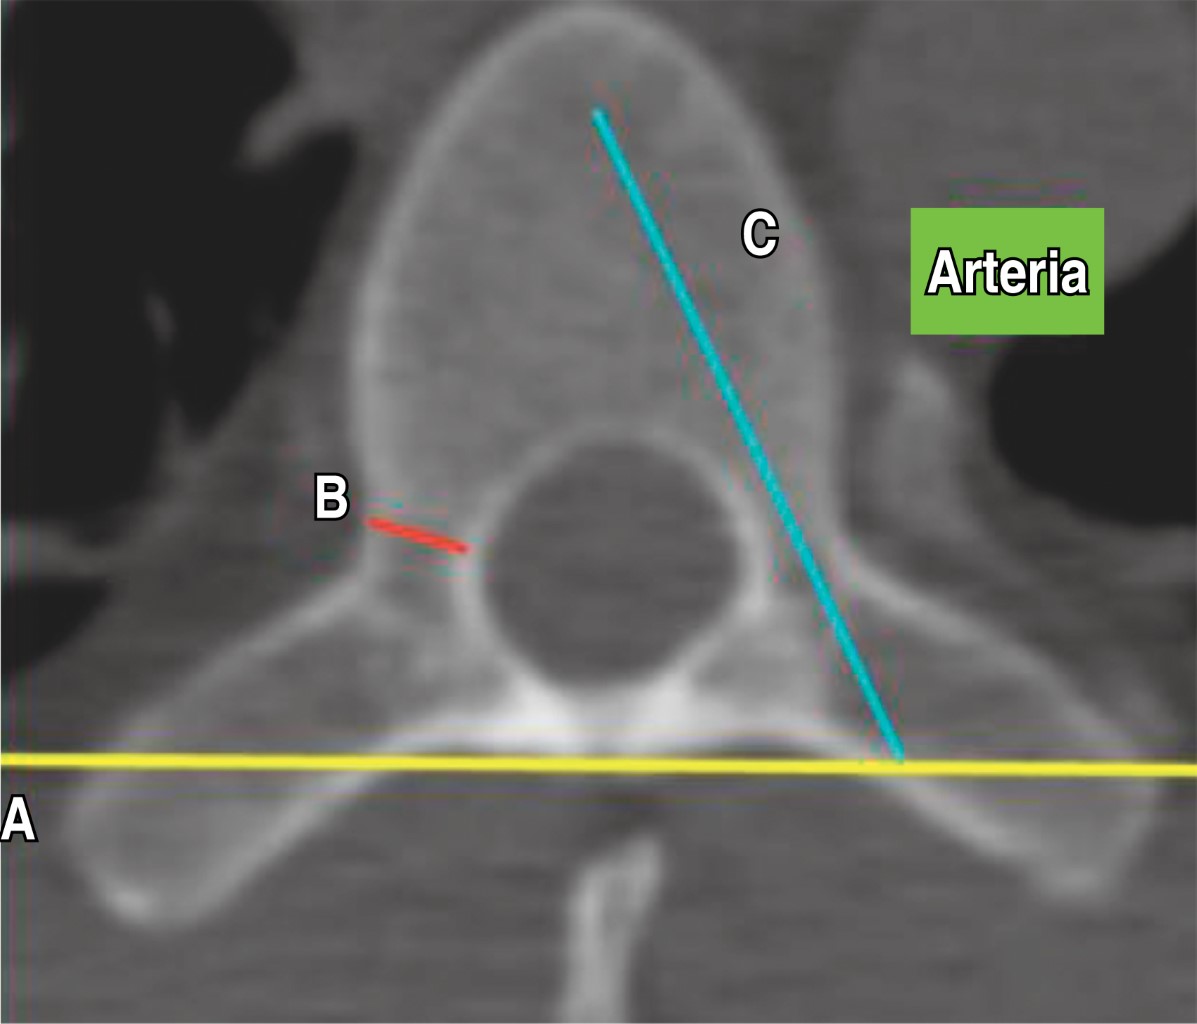

Se localizó el eje pedicular anatómico trazando una línea sagital que pasó por el punto medio de los diámetros transversal y sagital (línea C) del pedículo que va de anterior a posterior (Figura 1), y se midió el diámetro transversal del pedículo (DTP) a nivel del istmo que va desde la cortical medial a lateral (endóstico) en sus límites esponjosos (línea B).